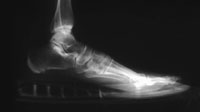

| Prolonged wearing can lead to Bunions, Hammertoes, Morton's Neuroma, and Achilles tendon shortening and tendonitis. |